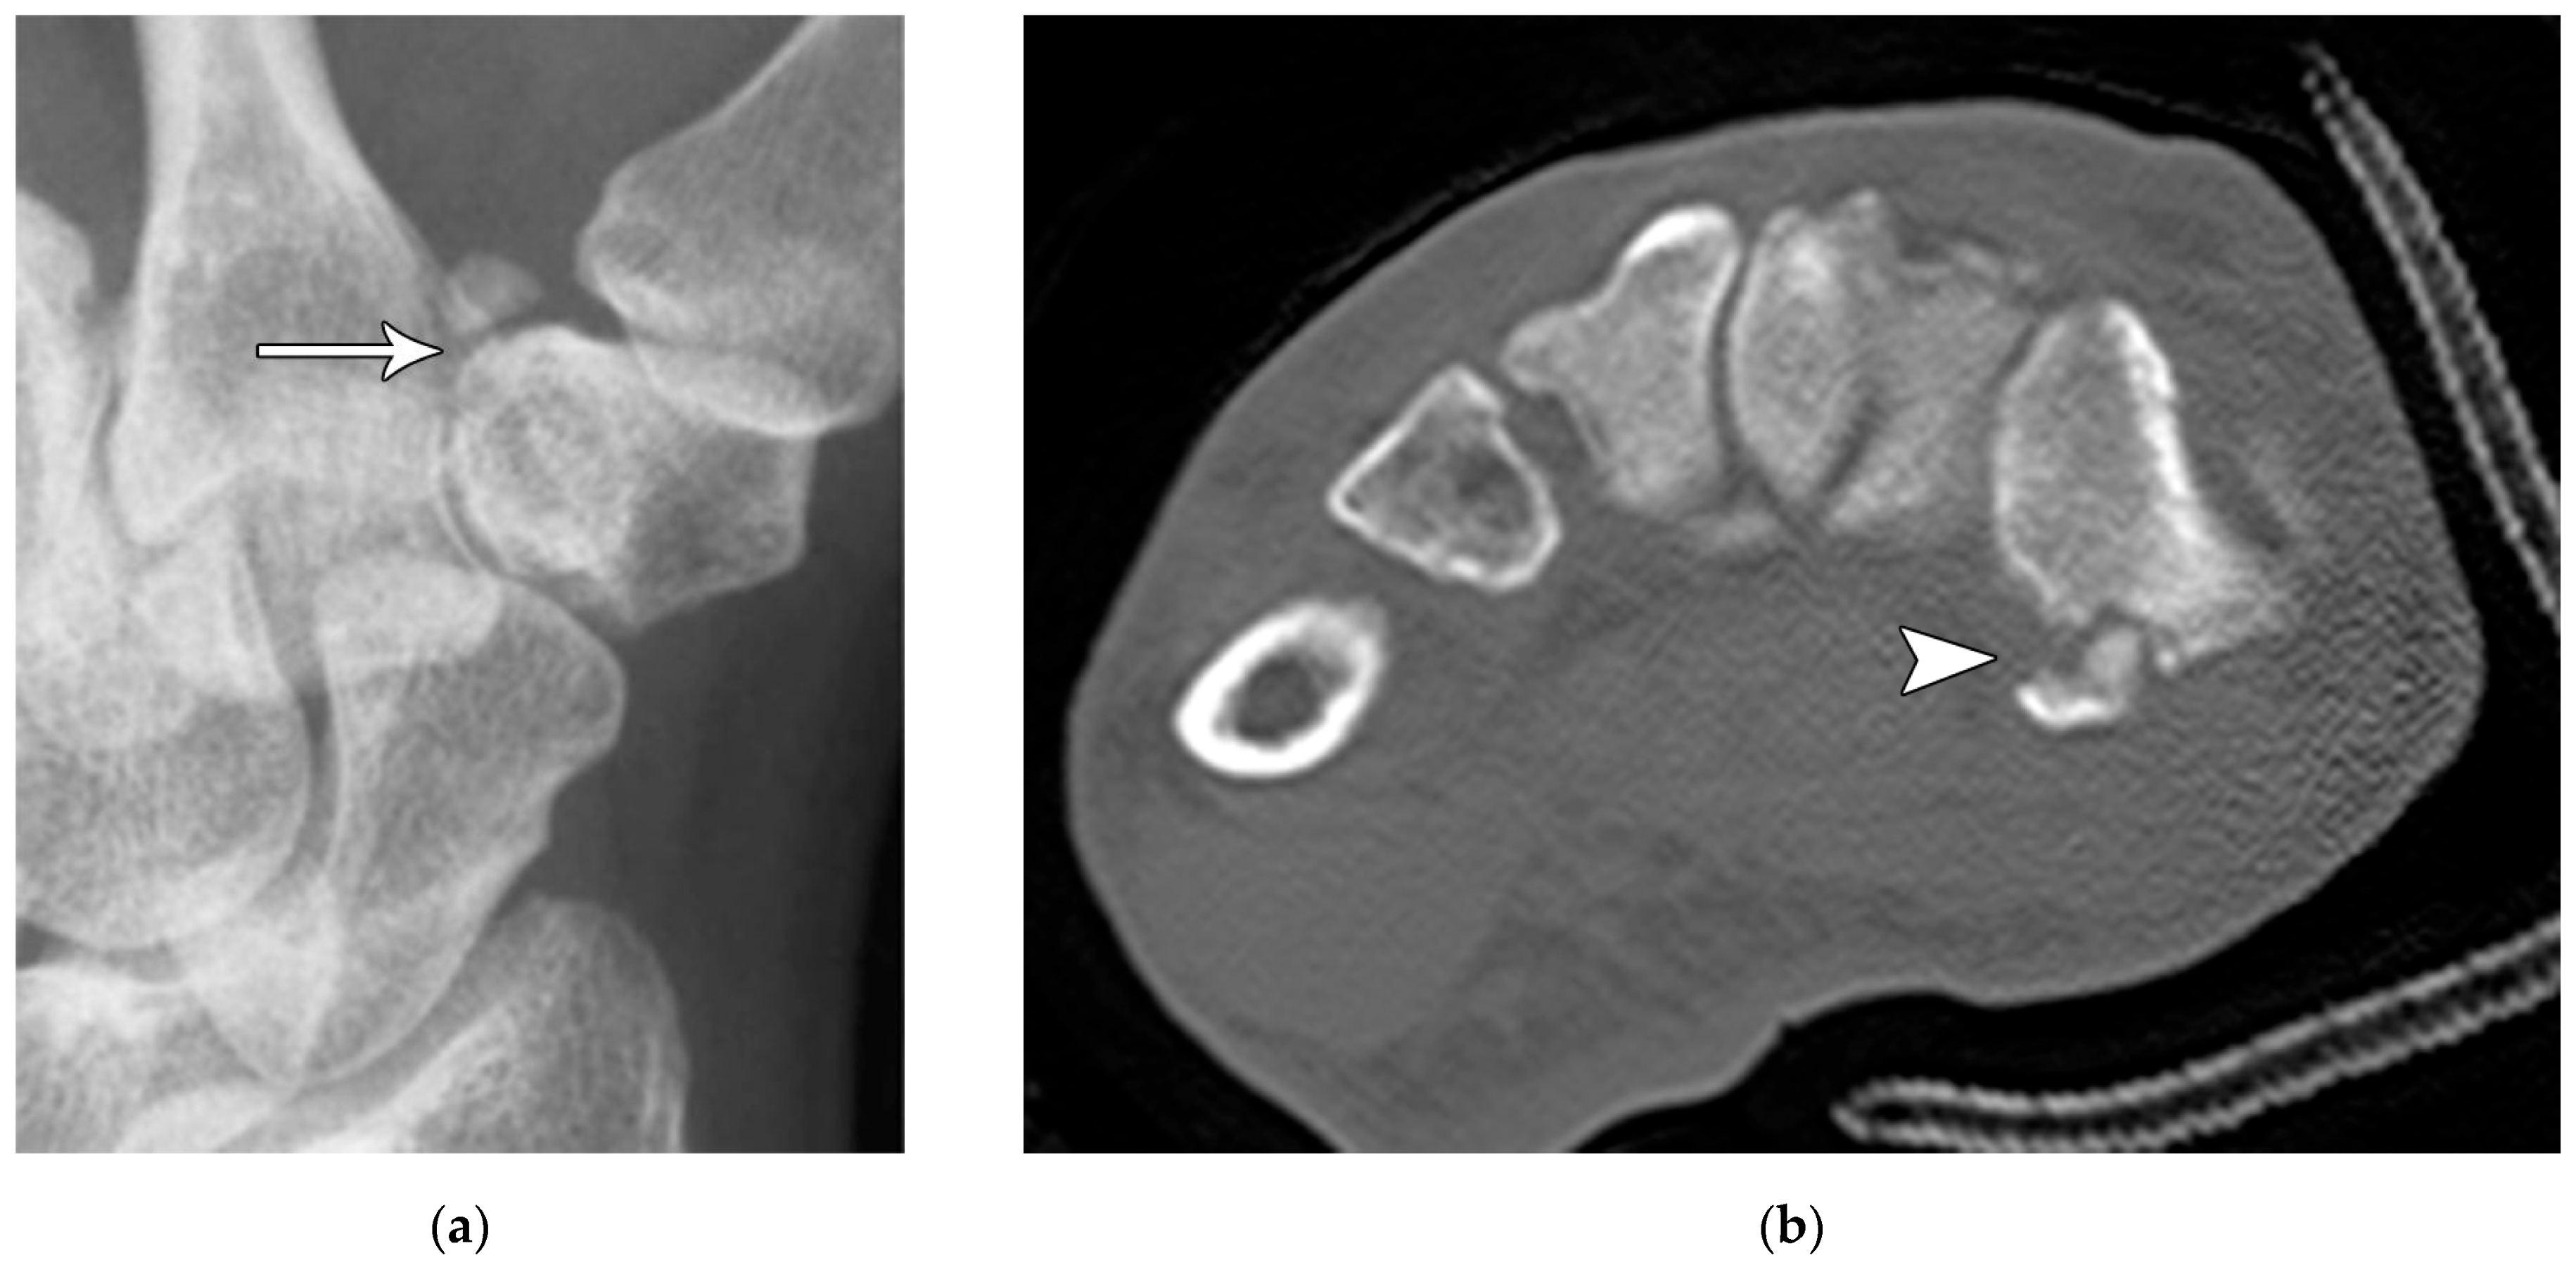

The majority of scaphoid fractures (70%) occur through the waist of the scaphoid, with 10% of scaphoid fractures involving the distal third, and 20% involving the proximal third (Figure 2 and Figure 3) [2,14]. With a scaphoid waist fracture, dorsal prominence at the fracture site due to dorsal angulation is known as humpback deformity (Figure 4). This deformity is important to recognize, as it needs to be more aggressively managed due to high risk of nonunion [15]. Additionally, if the two fragments unite with a humpback deformity, it may further destabilize the wrist. This humpback deformity may also be associated with dorsal intercalated segment instability (DISI), which will be covered in more detail later.

Figure 4. (a) Lateral radiograph of the wrist showing Humpback deformity (arrow) after a scaphoid fracture. (b) Sagittal CT reformation of the wrist showing the full extent of a humpback deformity with dorsal prominence at the site of the scaphoid fracture (arrowheads); image courtesy of Frank Gaillard, Radiopaedia.org, rID: 18269.